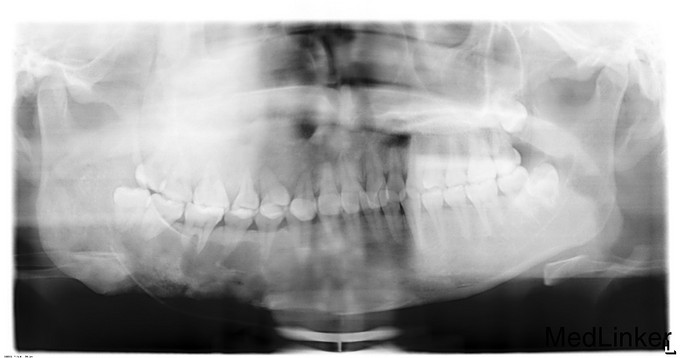

双侧颜面部不对称,右侧上下颌骨增大,质硬,双眼平视时存在复视,右眶下区、右下唇无麻木,右鼻无鼻塞,双侧髁突动度一致,开口度4cm,开口型正常,双侧颈部未扪及肿大淋巴结。口内检查:右下颌颊侧膨隆,右上颌颊侧、腭侧膨隆,余牙未见异常。CT示:右侧上、下颌骨、右侧颧骨、右侧蝶骨、蝶骨体、右侧额骨见明显膨胀性骨质破坏影,右侧髁突、冠突未见受累。骨破坏区边界大部分欠清,其内部密度高低不均匀,下颌骨病变处局部见类囊样低密影,余病变诸骨部分呈磨砂玻璃样密度影。病变区皮质菲薄、连续。右上颌窦、蝶窦窦腔完全闭塞。右侧鼻腔稍变狭窄,右侧眼眶底上抬。余左侧颌面诸骨未见明显骨质异常。诊断:右侧上、下颌骨、颧骨、右侧蝶骨、蝶骨体、右侧额骨骨纤维异常增殖症。